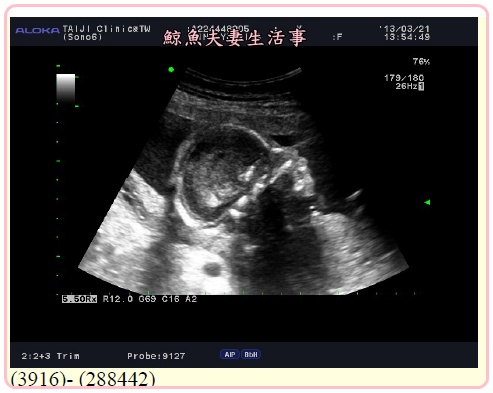

再來就是腹超照小朋友

助理放射師很溫柔的告訴我們每個細節

其實我都聽不懂也看不懂

只要放射師說正常正常媽媽我也就放心了

大概看了有半個小時

張醫生才進來再仔細檢查